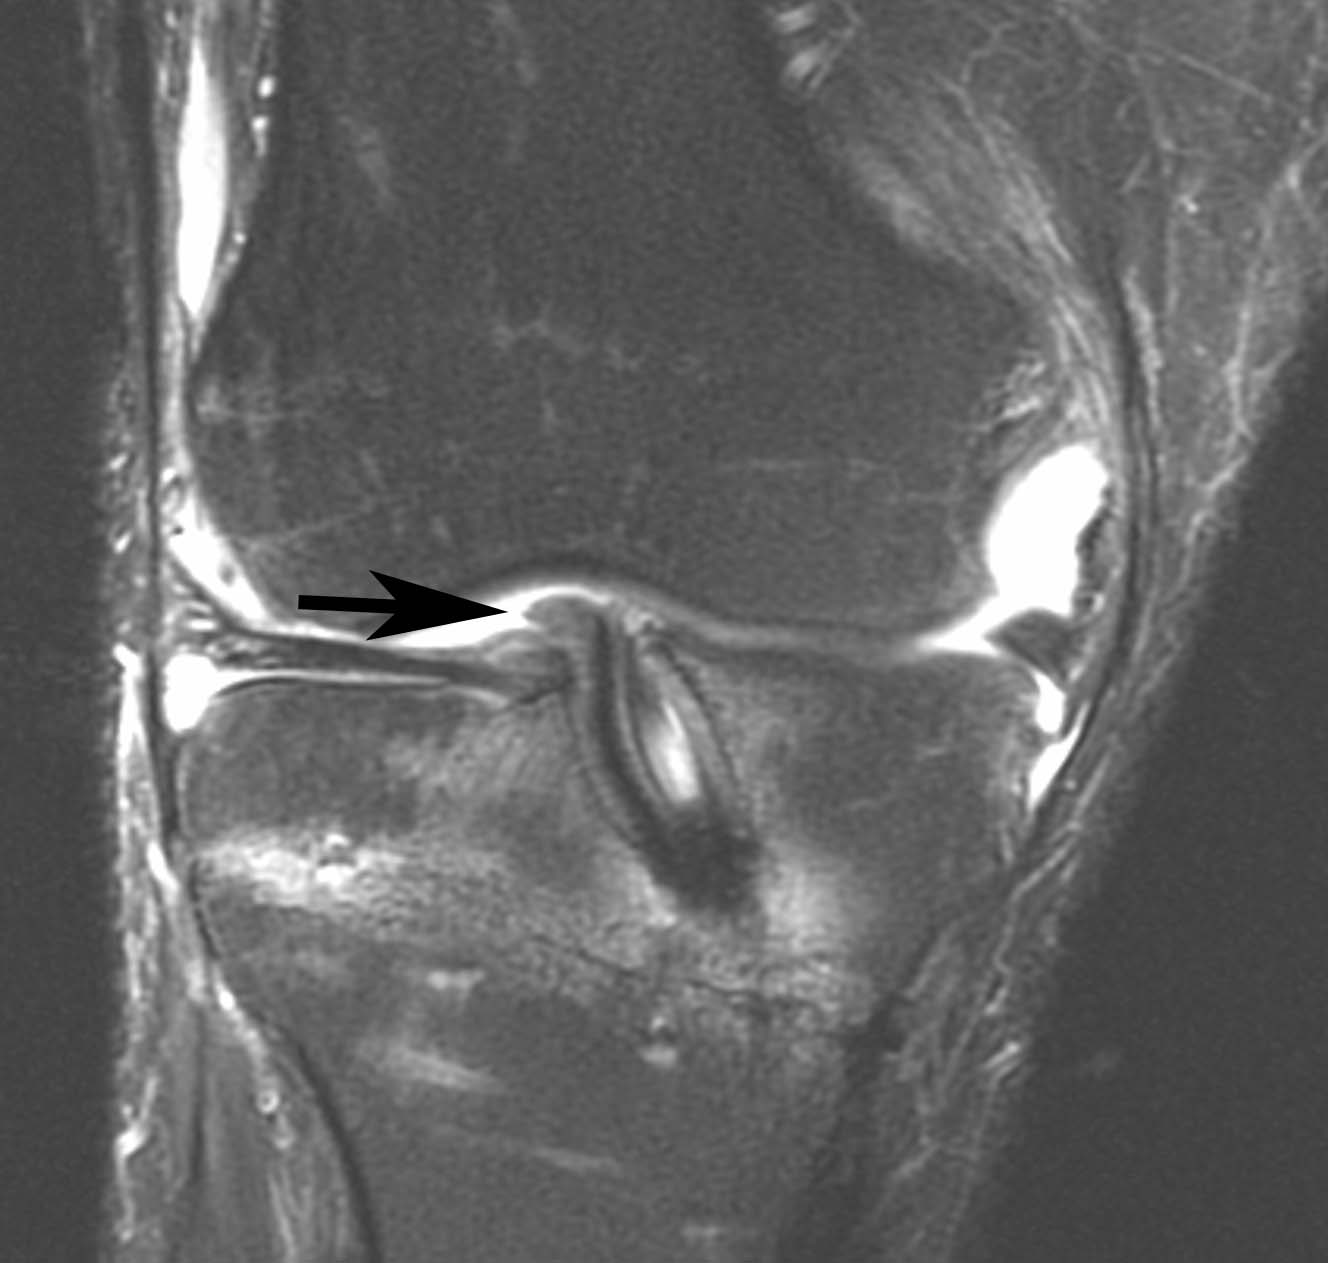

Figure 1 for case Disrupted ACL graft

Figure 1